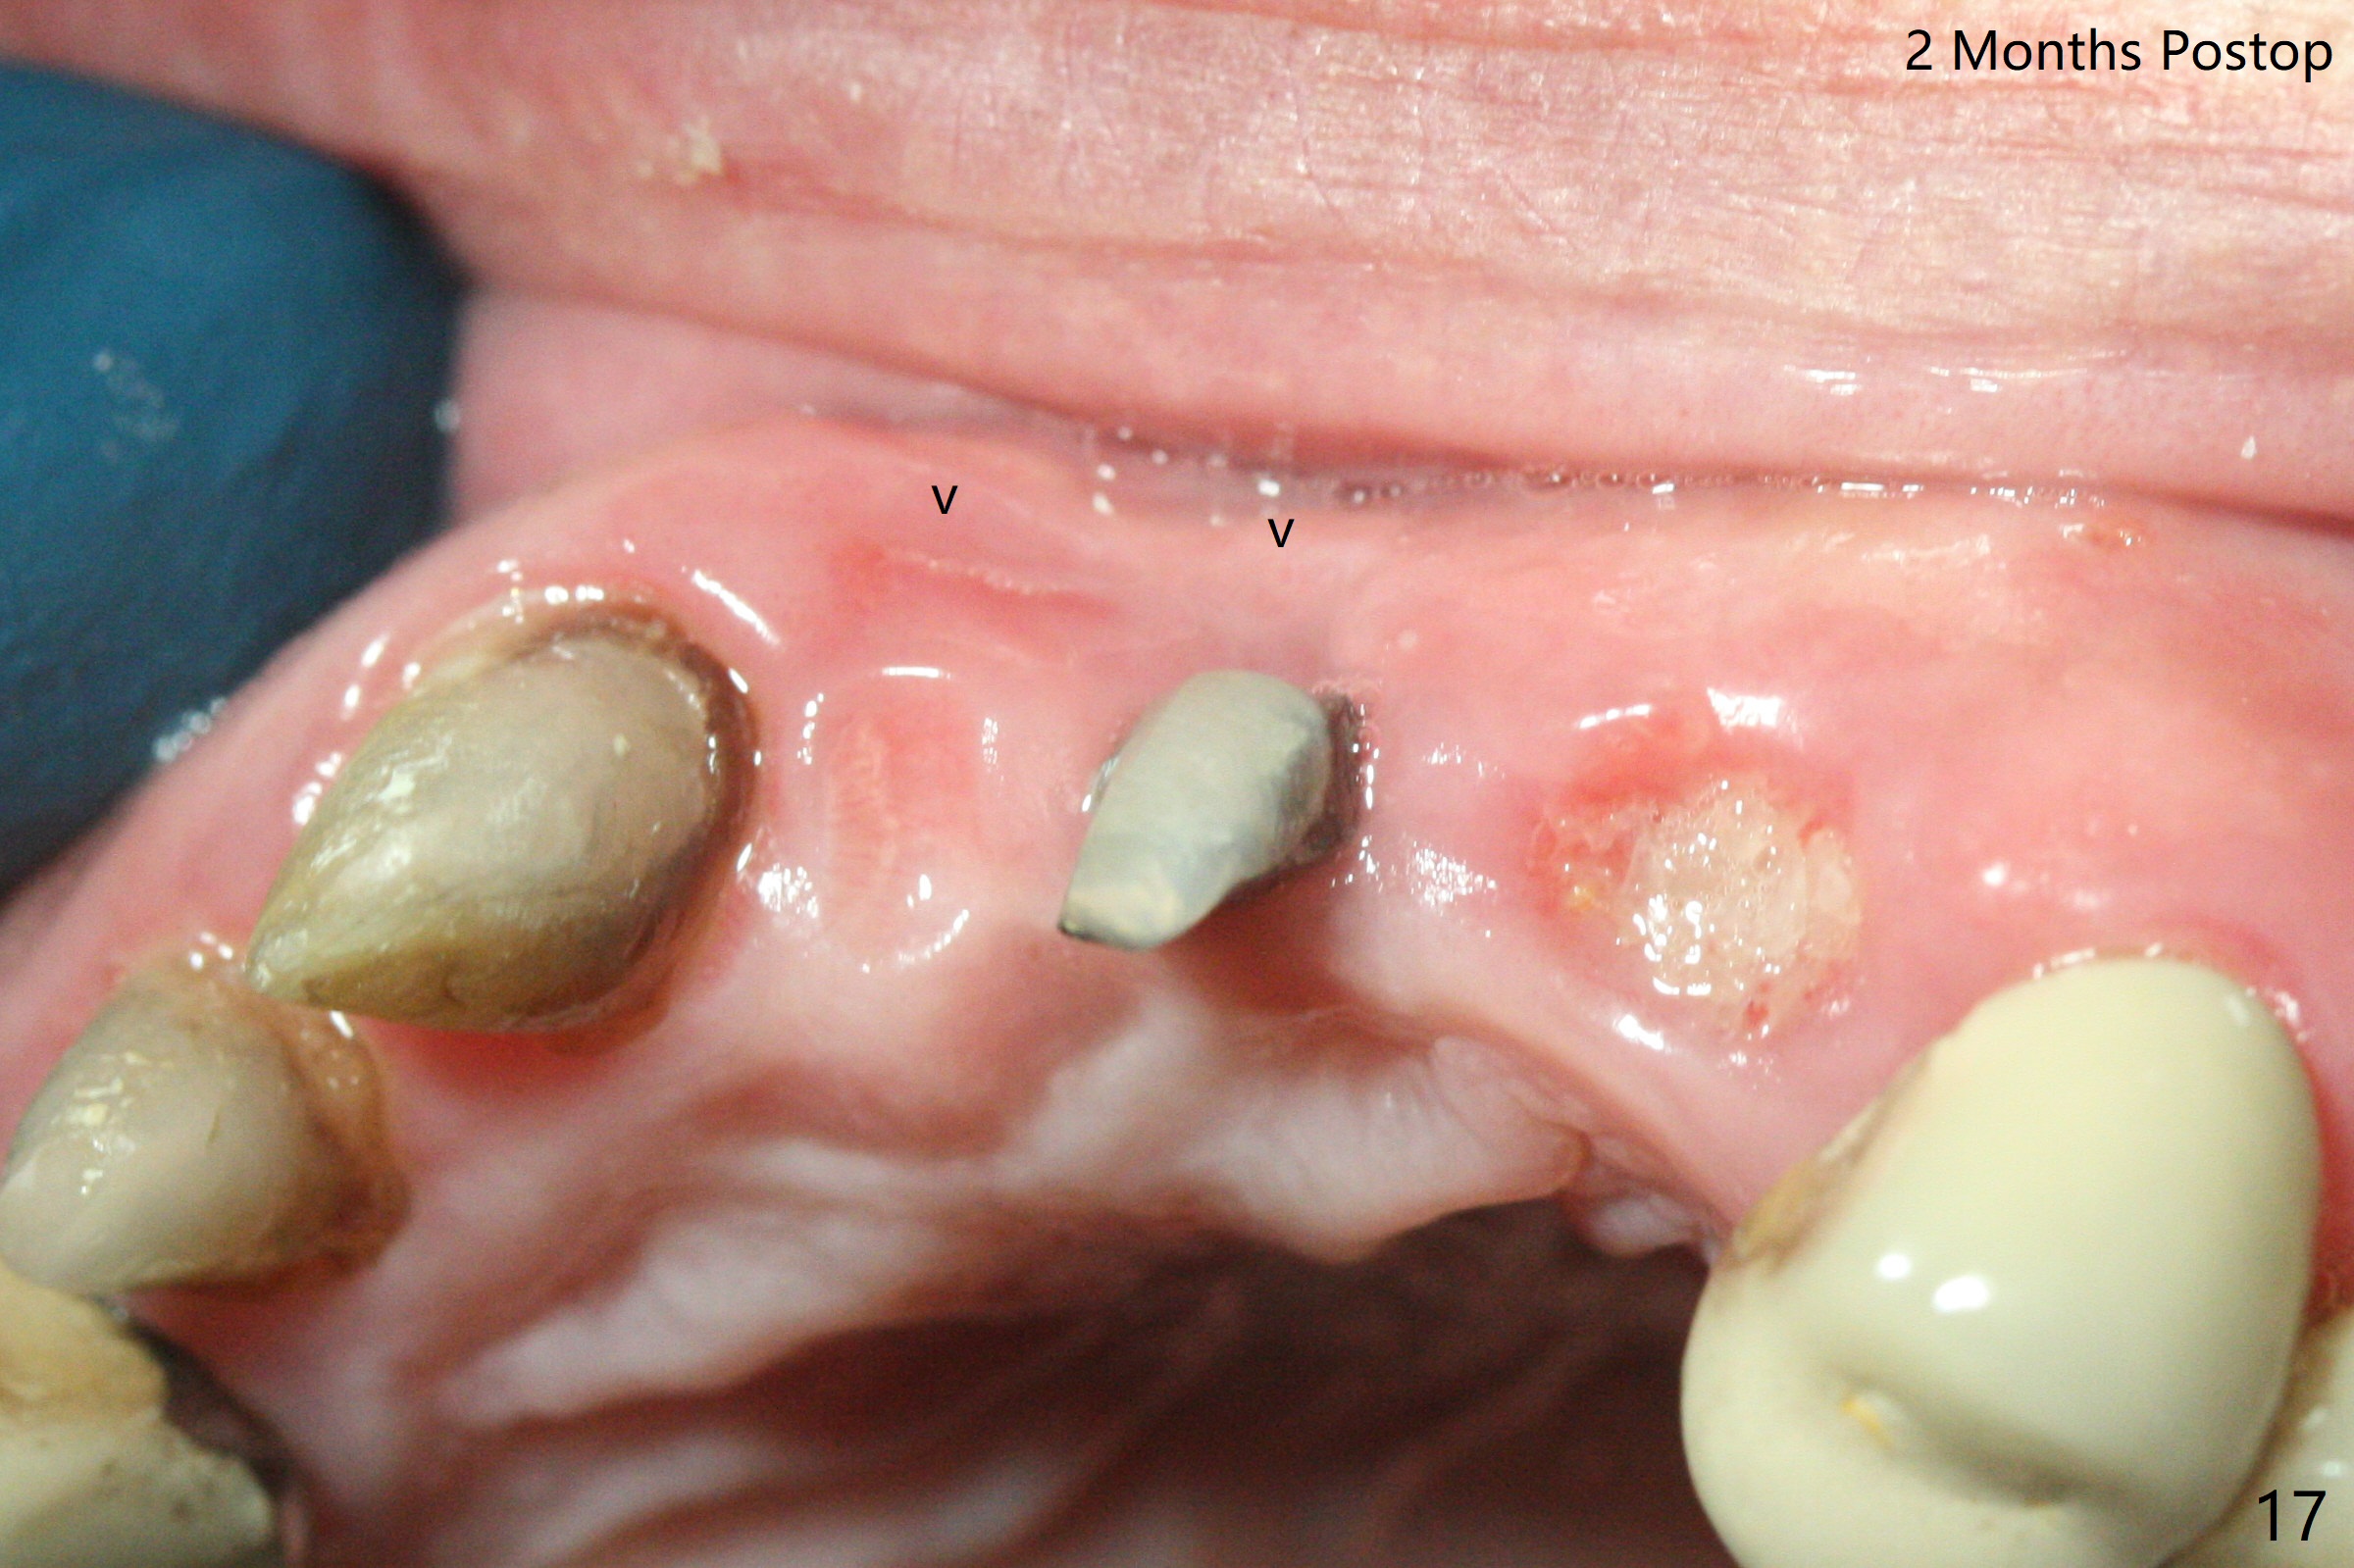

The mesiobuccal margin at #8 is redefined 4 weeks postop (Fig.14) so that the cervical end of the temporary crown is able to move mesially (Fig.13). The most coronal portion of the bone graft at #11 begins to be detached (*). The mesial portion of the abutment at #10 will be removed (curved white line) in the following week. After removing the most coronal portion of detaching bone graft at #11, acrylic is added to form a concave pontic (Fig.15 ^). With removal of the mesial portion of the abutment at #10, the retainer is moved distal (>). Pontics form at UL1 and 3 two months postop (Fig.16 *), while there is buccal atrophy at UL1,2 (Fig.17). 术后3个月植牙区牙龈形态良好(图十八),即将暴露,放置愈合基台。图十九是在右上1根管治疗时(基台放置后五天)拍摄。左上3术后3个月3个星期,1,2唇侧塌陷(图二十)。叶状植体处牙槽嵴往根尖萎缩(图二十一:^)。尽管做了松弛切口,放入事先预备的粘性骨粉后,几乎没有空间放置结缔组织移植物,恰好还没有取。放置PRF膜后,使用4-0 Monoglyc缝线缝合。牙龈似乎冠方移位(图二十二:箭头)。植骨后,唇侧仿佛饱满多了(图二十三:*)。骨粉放置于左上1,2唇侧和牙槽嵴(图二十四:*,与之前(图十九)对比)。后者有助于牙龈冠方移位,而前者有助于增加唇侧饱满度。植骨术后两周唇侧仍饱满(图二十五,六)。植骨后四个月牙冠粘固,两个月后,病人抱怨10号牙左右食物坎塞(图二十七),9/10牙冠撤除,10基台边缘加深,重做临时牙冠,同时增加9凹陷(pontic)。一个月后,9/10临时牙冠修整两次,11永久性牙冠撤除,也制备临时牙冠,外形明显改善(图二十八)。